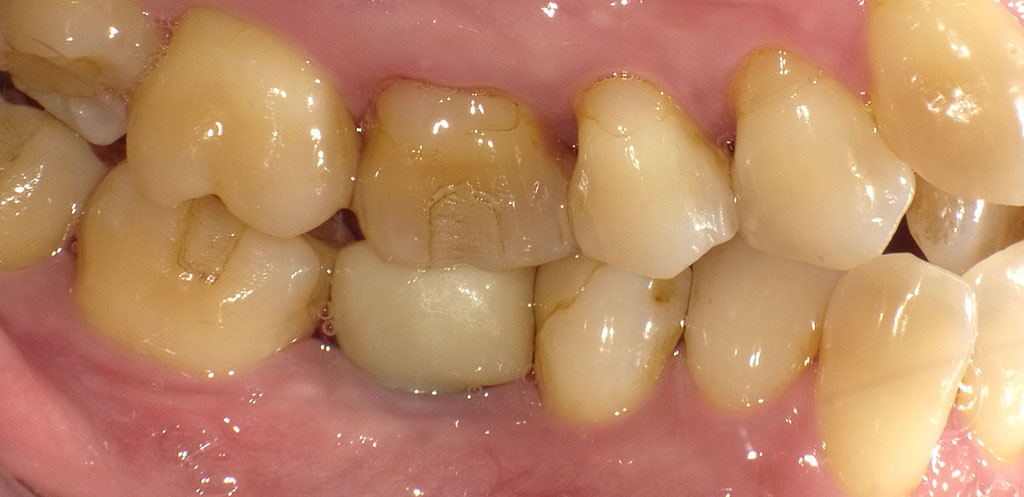

After1

After2

フラップレス手術にて、右下6番の骨にインプラントを埋め込みました。インプラントと骨がしっかり結合するまで3ヶ月待ち、インプラントの上に人工の歯を被せる治療を行いました。